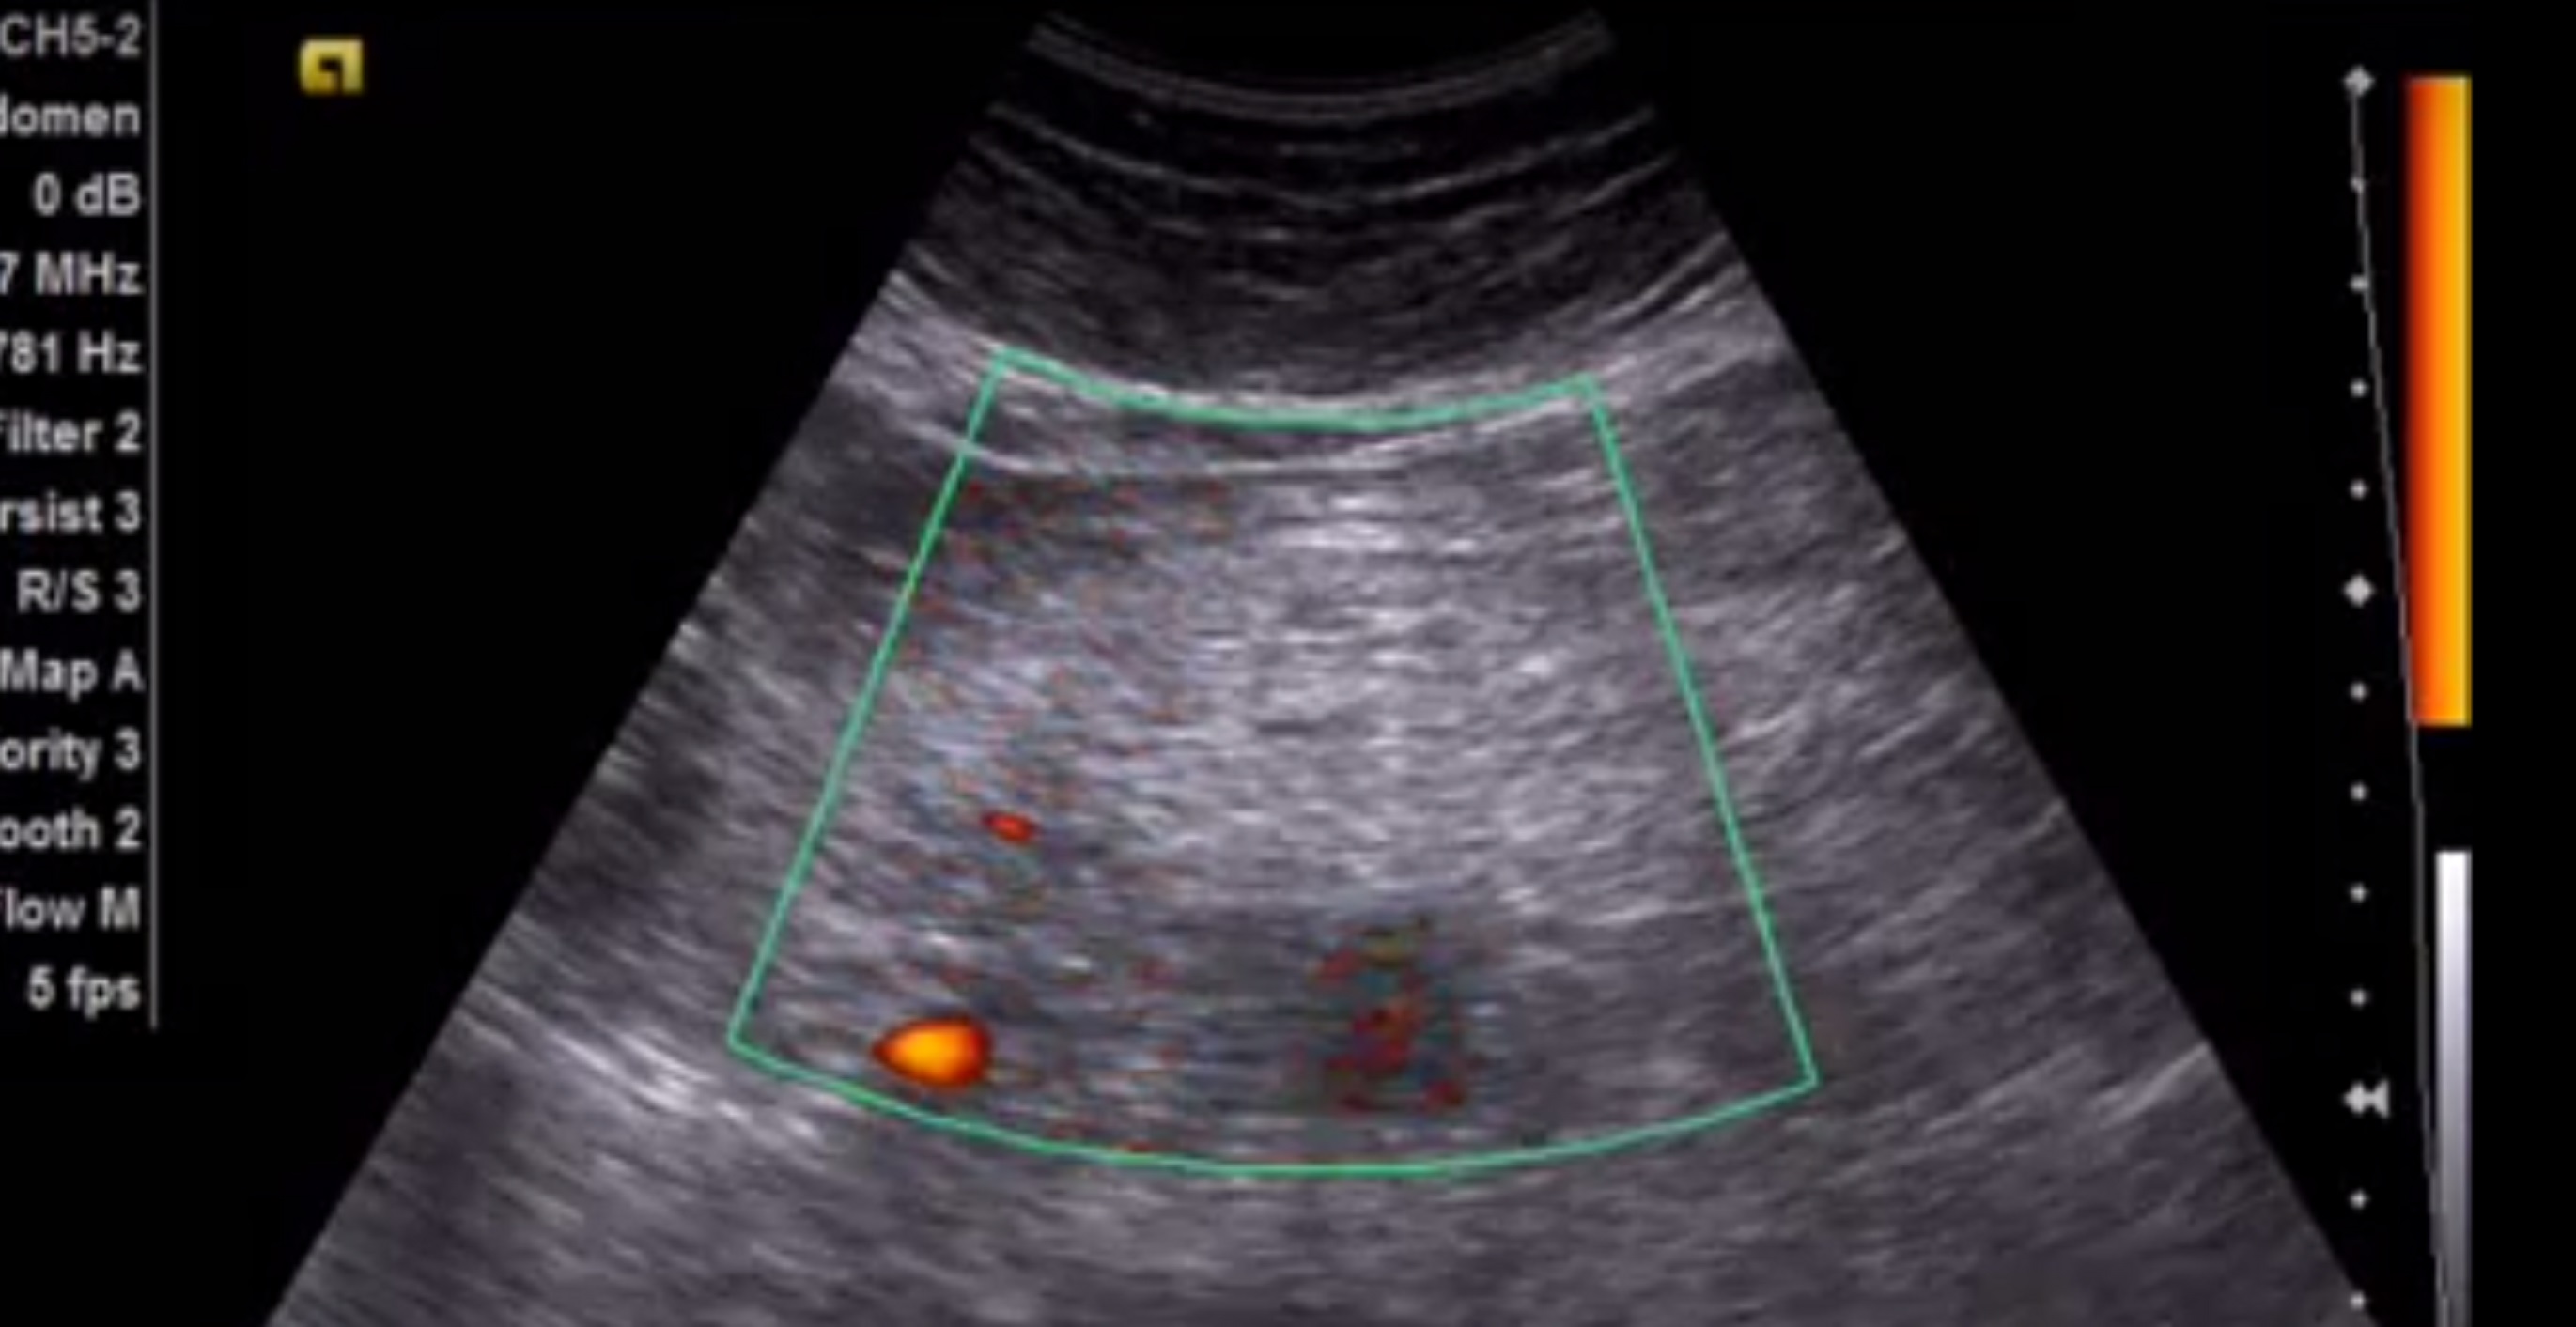

описание:

в проекции поперечно ободочной кишки, лоцируется фрагмент гиперэхогенного сальника , размером 12*4 см, с признаками кровотока на ЭДК

Заключение Уз признаки воспалительных изменений фрагмента большого сальника(инфаркт?)

посмотрите эхограммы, пожалуйста. В ролике можно сравнить эхогенность сальника в указанной области и правее